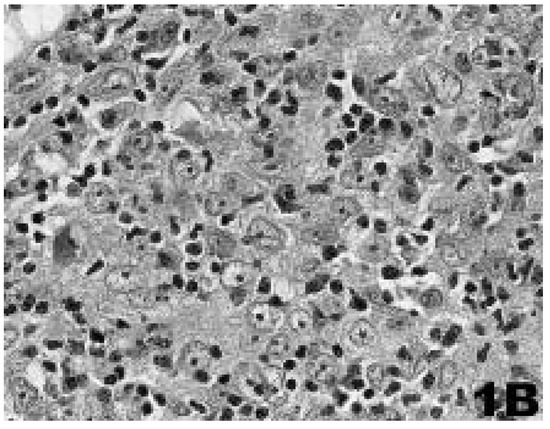

Case Report

Life-threatening myasthenia gravis masked by a psychiatric disorder

by Stephan J. Rüegg, S. Dirnhofer, C. H. Buitrago-Tellez, A. J. Steck and S. Marsch

Swiss Arch. Neurol. Psychiatry Psychother. 2007, 158(4), 150-154; https://doi.org/10.4414/sanp.2007.01850 - 1 Jan 2007

Cited by 4 | Viewed by 62

Abstract

The coincidence of a psychiatric and a neurological disorder in the same patient may be an especially challenging clinical situation [...] Full article

Show Figures

Figure 1